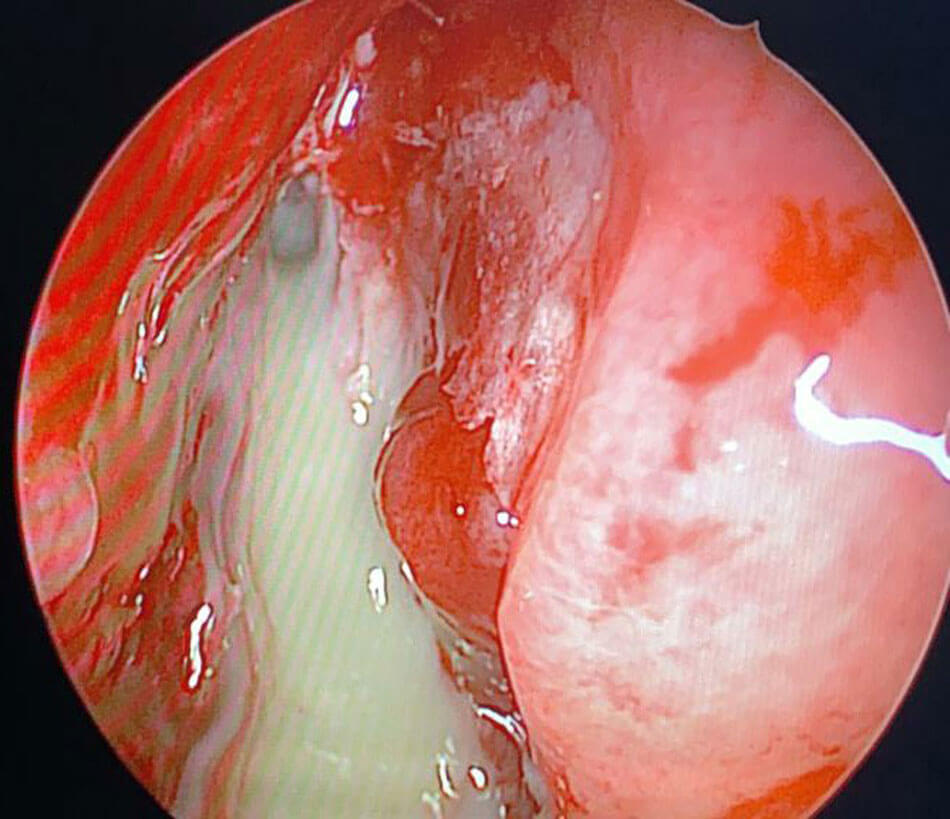

Endoscopic picture of mucor with necrotic tissue in middle meatus.